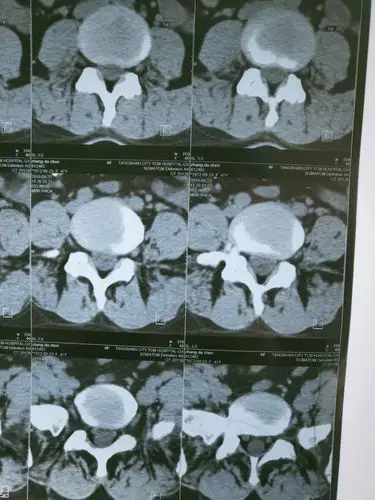

腰椎间盘ct平扫(l5-s1)